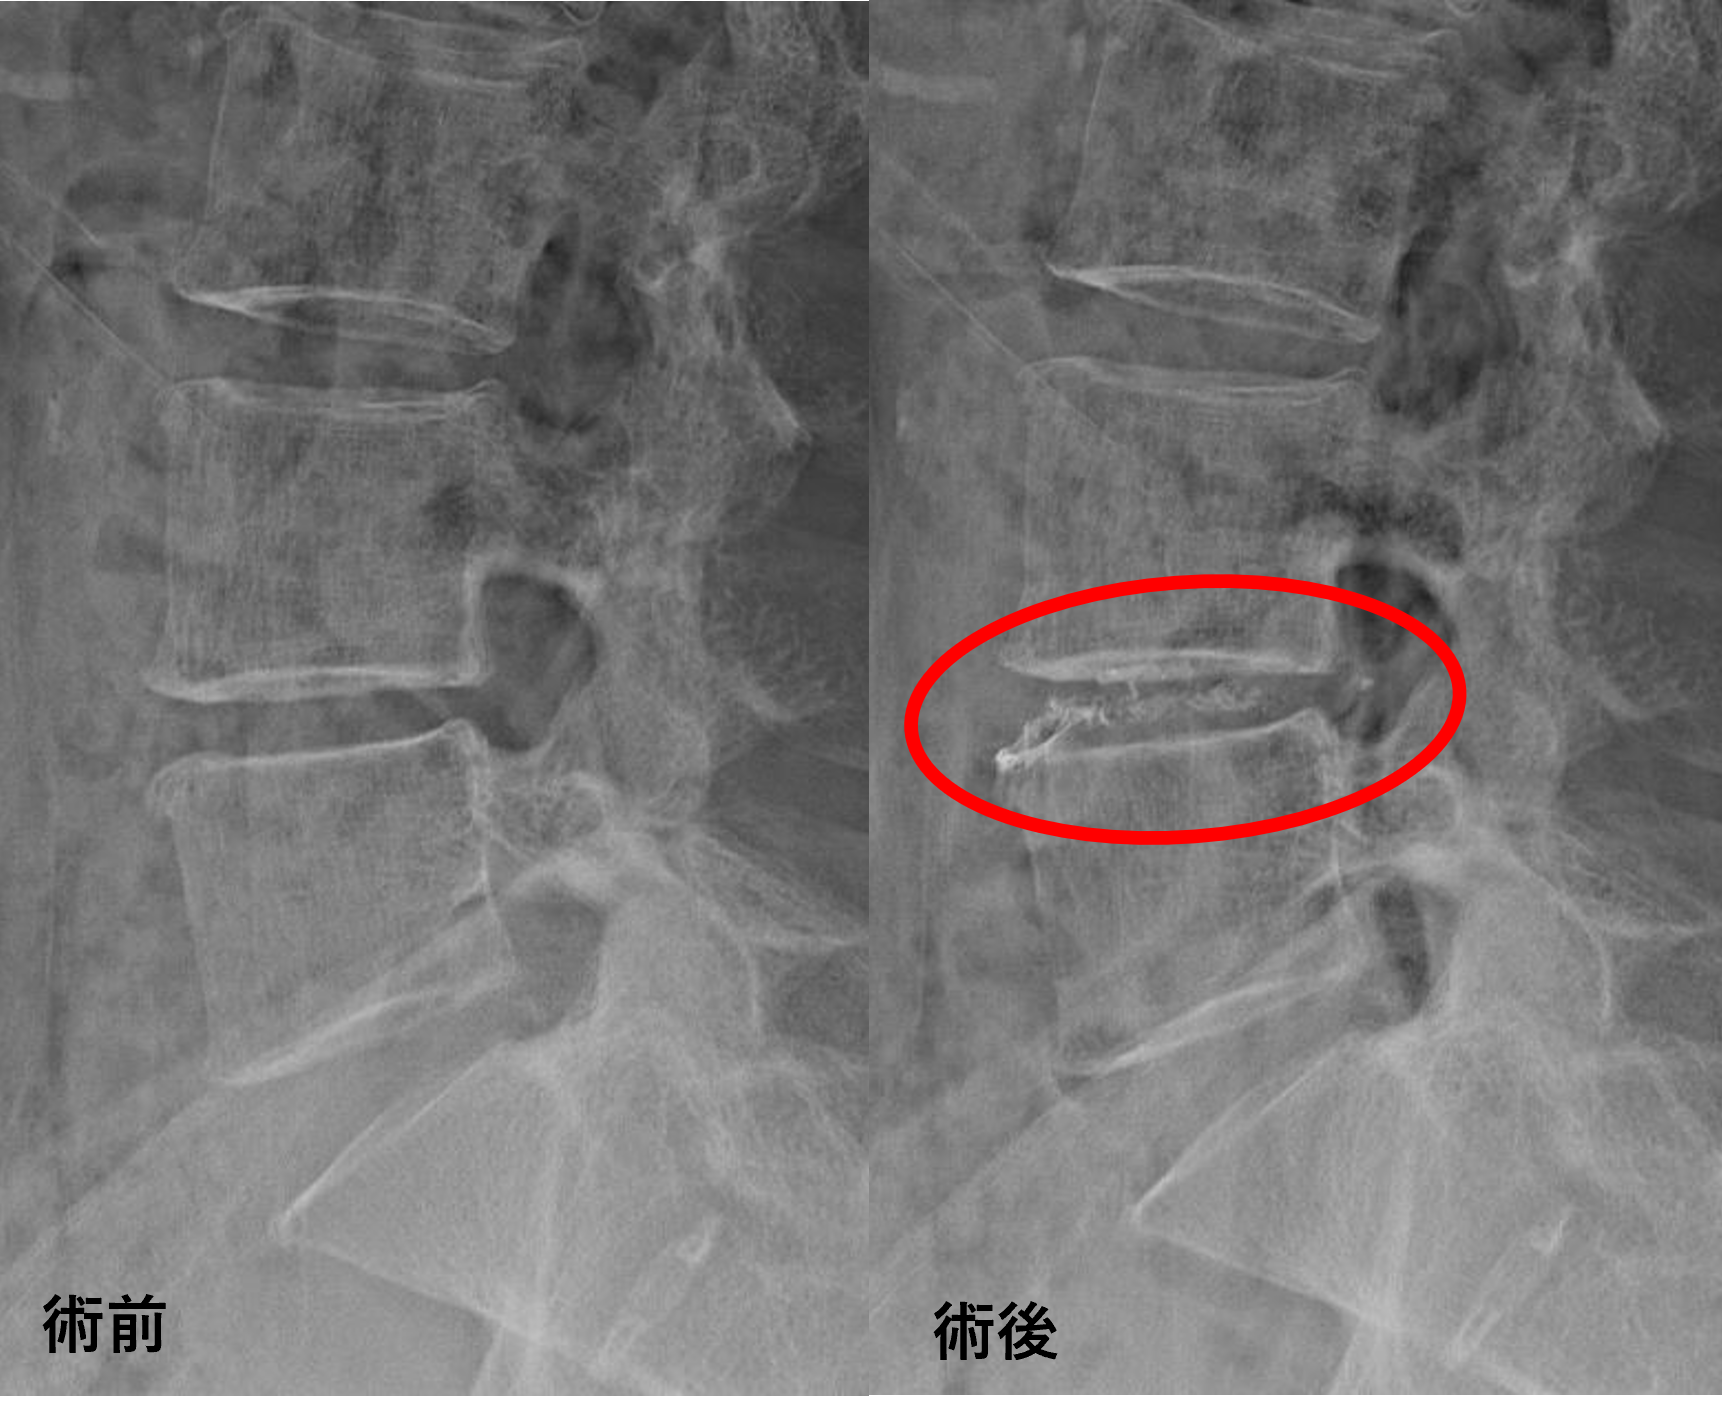

画像及び所見について

- L4/5 – 椎間板変性、膨隆、椎間孔狭窄

以上のことが画像上認められました。

L4/5の椎間板所見による脊柱管の圧排が、症状の原因の可能性が高い。

患者様と相談の元、L4/5にセルゲル法を施行